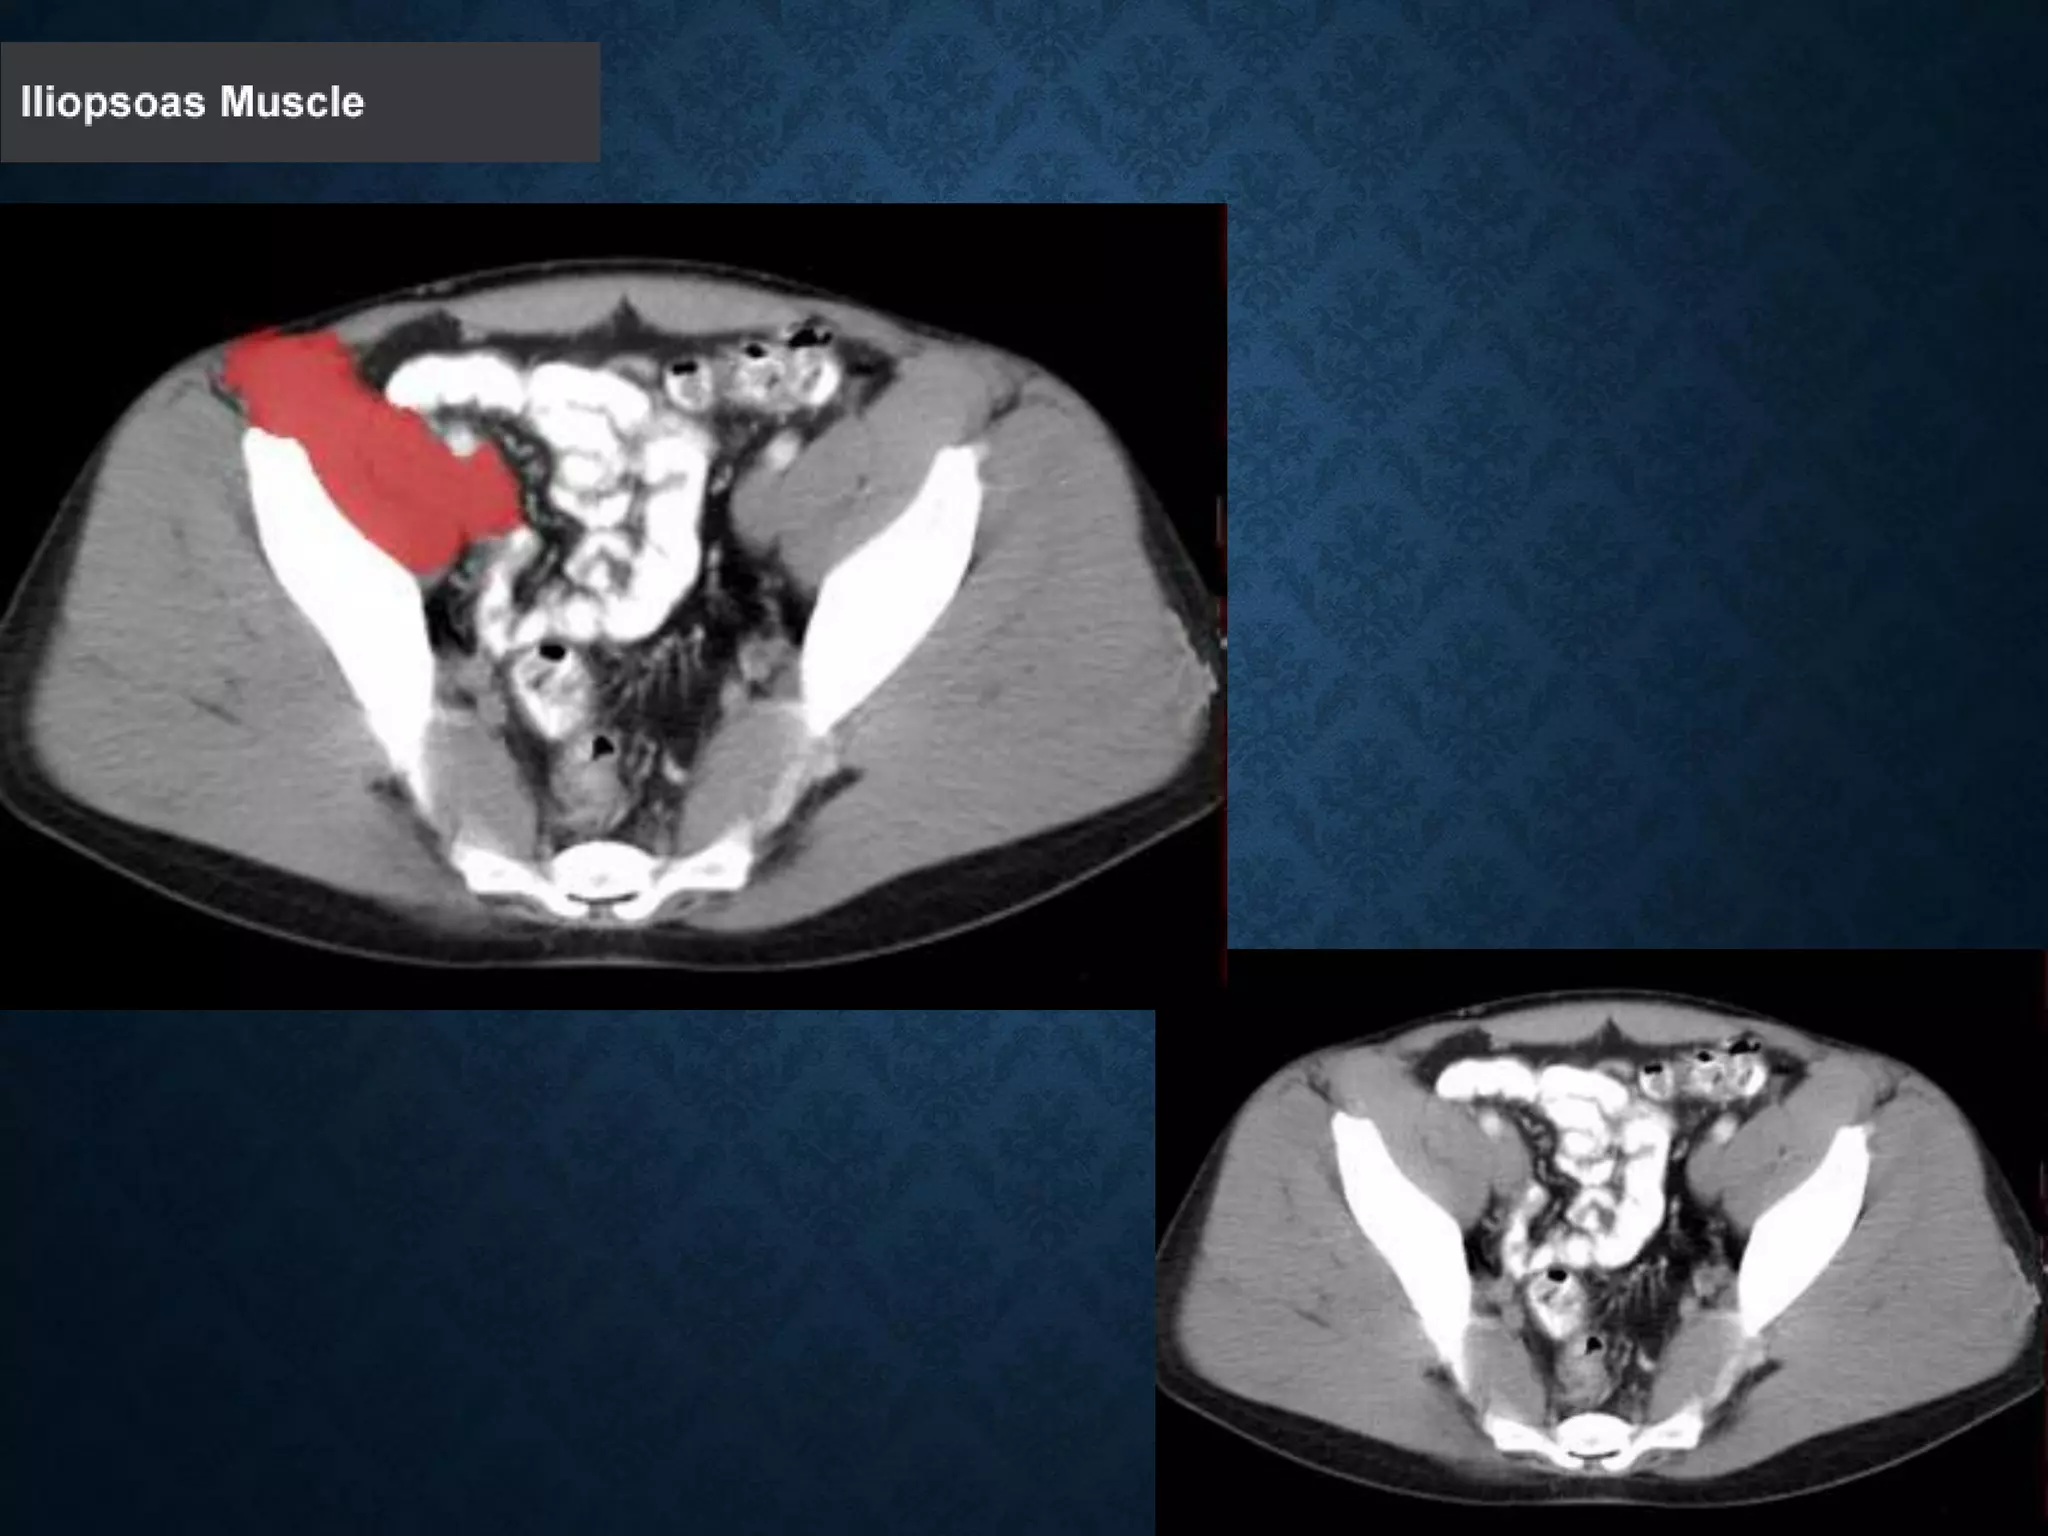

Identify the following structures in the body CT to the right. To view the location of the structure in the image click on

the label at the left and the structure will be indicated in the image. Abdominal CT scans typically begin just above

the diaphragm, so the first slice you see is of the lower chest.